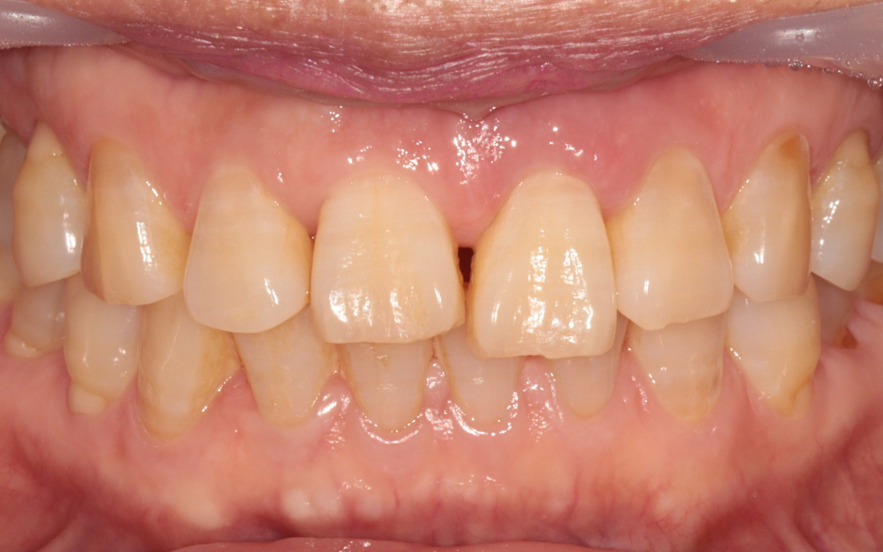

처음 내원하셨을 때의 상태입니다. 앞니 파절로 인해 치료가 시급한 상황이었습니다.